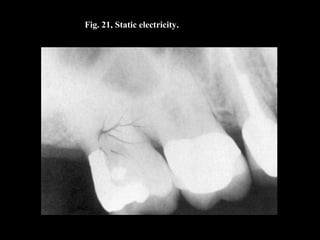

Fig. 21, Static electricity.